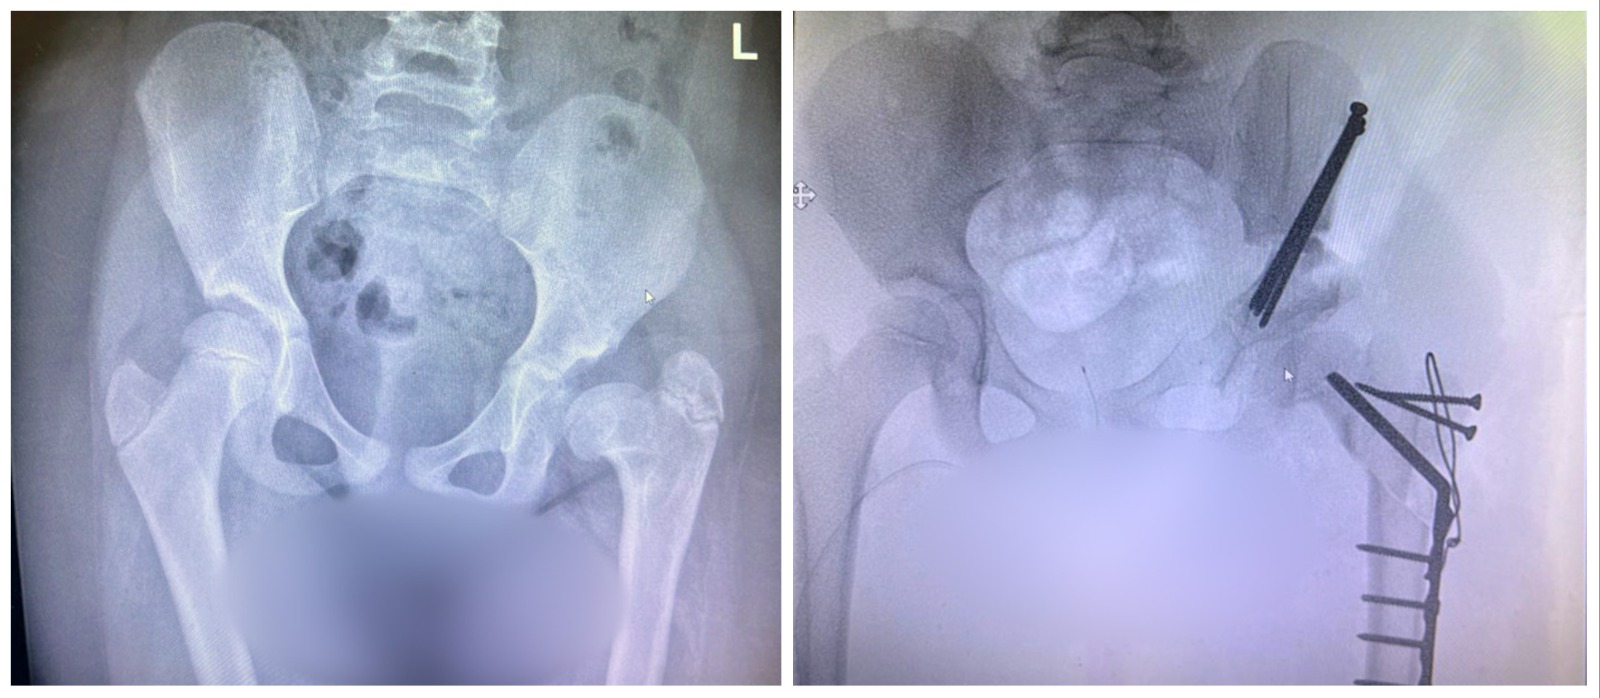

It took many months to arrange for Amal’s arrival in Israel and her surgery at Rambam. Finally, a few days ago, Professor Eidelman and his multidisciplinary team performed the complex procedure of lengthening her thigh bone (femur). “Amal’s surgery was challenging, but we were successful, and it ended well,” Eidelman adds. “We repaired her femur with a plate, screws, and an implant. Following the surgery, we immediately noticed an improvement in her condition. She can now walk again, has less pain, and is able to enjoy her life. Amal is calm and her parents are delighted. After being discharged, the family returned to Jordan, and in six-weeks, Amal will return to Israel for a follow-up visit at Rambam. I am very optimistic.”

The Pediatric Orthopedics Unit at the Ruth Rappaport Children’s Hospital at Rambam is the only center in Northern Israel treating disorders of the musculoskeletal system in children. The hospital specializes in skeletal trauma, deformities, limb elongation, clubfoot, and early detection and treatment of congenital dislocated hips.